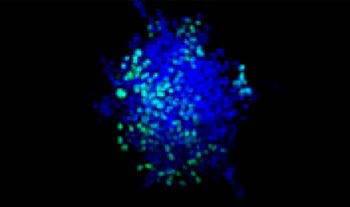

Making the spheroids transparent and imaging them with an FV3000 confocal laser scanning microscope enabled us to image the co-cultured cancer spheroids at depth. Staurosporine treatment increased the number of dead cells in a dose-dependent manner (Fig. 2*1). Three-dimensional analysis is required to determine which cells are dead and how many dead cells there are in a three-dimensional mass.

Figure 2. Drug response in co-culture spheroids

Figure 2. Drug response in co-culture spheroids*1